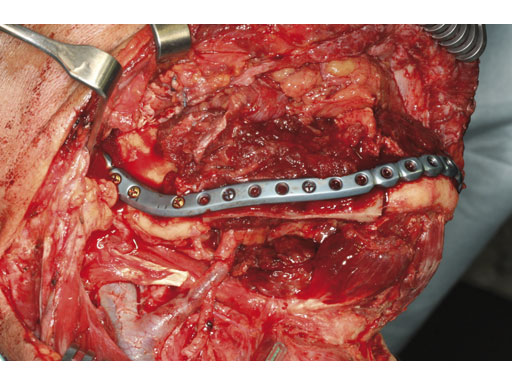

Case 2: A 65-year-old man suffering from an oral cancer in the anterolateral floor of the mouth with infiltration of the right mandible. The preformed reconstruction plate was applied to the lateral surface of the hemimandible prior to en bloc tumor resection, including a bone segment via extended submandibular access. The missing bone was replaced with a revascularized scapula border in combination with a soft-tissue parascapular flap. The patient has had no recurrence 1.5 years postoperatively.

Fig 4 Primary fixation of implant, serving as a load-bearing bridge over the bone gap.

Fig 5 Reconstruction with revascularized scapular border composite flap.

Case provided by Carl-Peter Cornelius, Mnchen, Germany